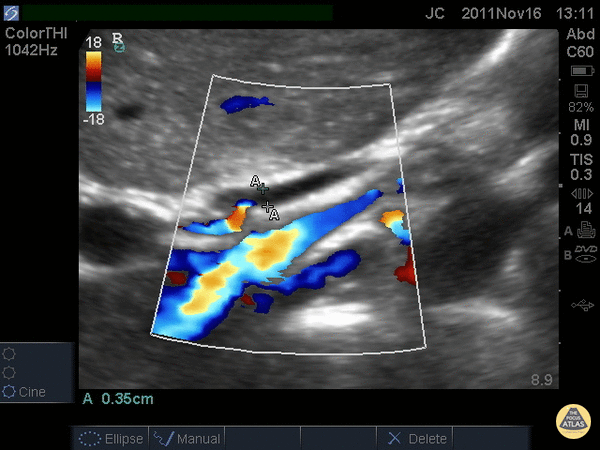

Biliary - Common Bile Duct (Normal)

When searching for the common bile duct (CBD), color doppler can be useful to differentiate vascular structures from non-vascular structures. In this case the CBD is being measured anteriorly and does not have any pulsations on color doppler. The portal vein and artery can be seen and with the CBD, make the portal triad. A normal CBD should be less than 4mm plus 1mm per decade after 40 years old. It should be measured inner wall to inner wall. Justin Bowra MBBS, FACEM, CCPU Emergency Physician, RNSH et al. (Dr. Chiang)